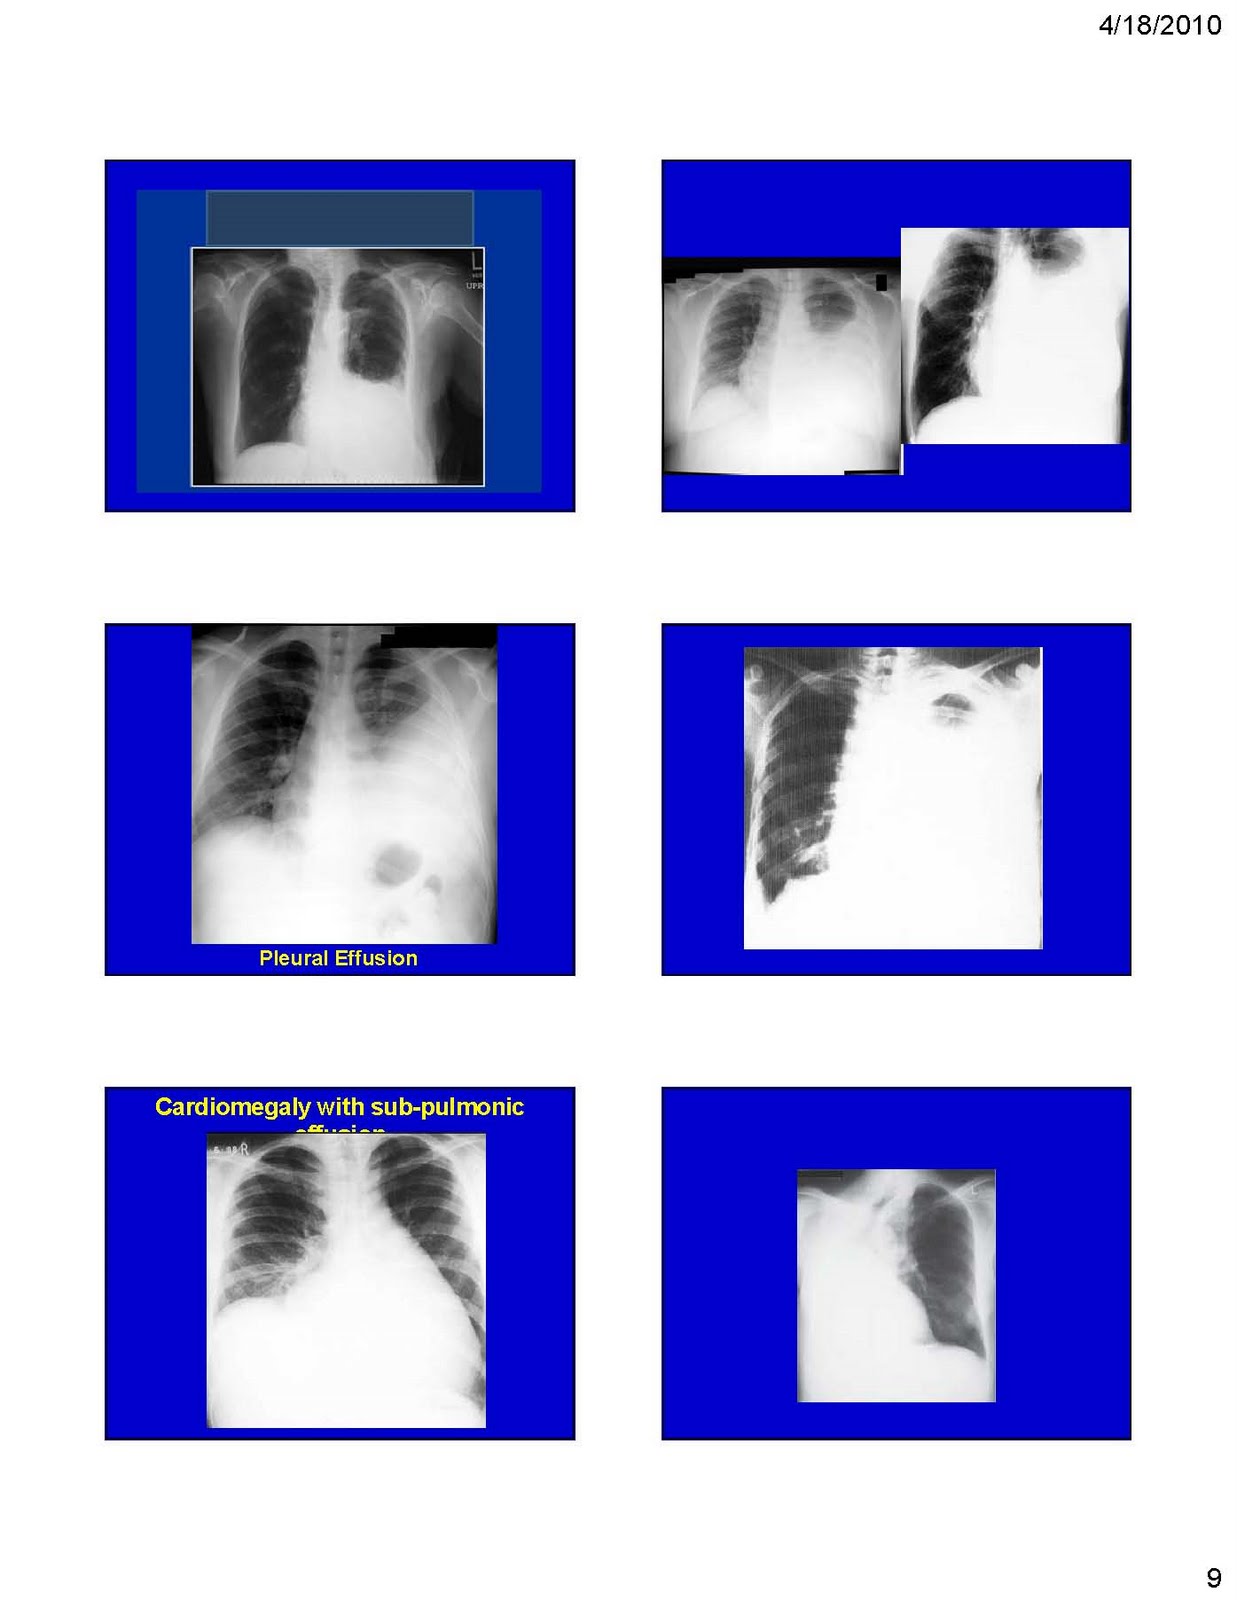

Pleural effusion Respiratory therapy, Pleural effusion, Radiography Respiratory X-Ray Interpretation Doctors typically use this procedure to help diagnose breathing difficulties, a bad or. The chest radiograph remains one of the most commonly performed examinations in radiology. It is typically the first. In fact every radiologst should be an. It is performed standing and in full inspiration. Respiratory X-Ray Interpretation.